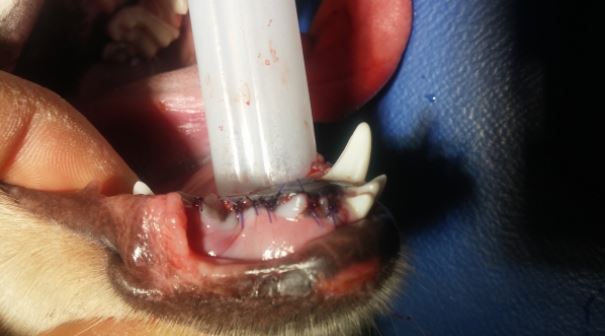

*L’extraction fermée peut être définie comme une avulsion sans retrait d’os alvéolaire. La cavité d’extraction est soit laissée ouverte pour une cicatrisation par granulation soit fermée en suturant la gencive au dessus de l’alvéole pour obtenir une cicatrisation par première intention.

*L’extraction ouverte ou chirurgicale se caractérise par le retrait d’une partie de l’os alvéolaire se trouvant au dessus de la racine dentaire pour faciliter l’extraction de la dent. La cavité d’extraction est ensuite suturée pour une cicatrisation par première intention.

Toutefois, même si une technique d’extraction fermée est utilisée, la gencive peut être suturée au dessus de l’alvéole dentaire. Dans ce cas, la rugine est d’une très grande aide pour libérer la gencive permettant ainsi une suture sans tension.